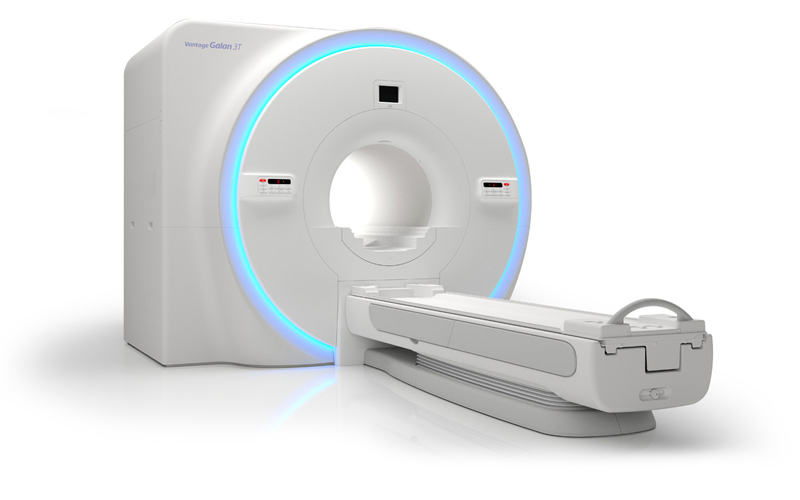

Vantage Galan 3T MR от Canon Medical Systems создана для получения высококачественных изображений и оптимизации рабочего процесса врача-диагноста. Комплекс различных технологий позволил создать тихую, быструю и экономичную МР систему.

МРТ аппарат Vantage Galan 3T MR дарит пациенту ощущение свободы во время исследования.

Диаметр отверстия 71 см обеспечивает достаточно пространства между пациентом и внутренней частью отверстия и создают ощущение открытости. Широкий туннель позволяет обследовать пациентов даже крупного телосложения. Комфорту способствует и большое свободное пространство перед лицом.

Vantage Galan 3T предлагает иммерсивную опцию MR Theatre, которая создает уникальную среду, помогая максимизировать комфорт и успокоить пациента.Использование «виртуального театра» MR Theater, позволяет демонстрировать расслабляющие изображения по время сканирования.